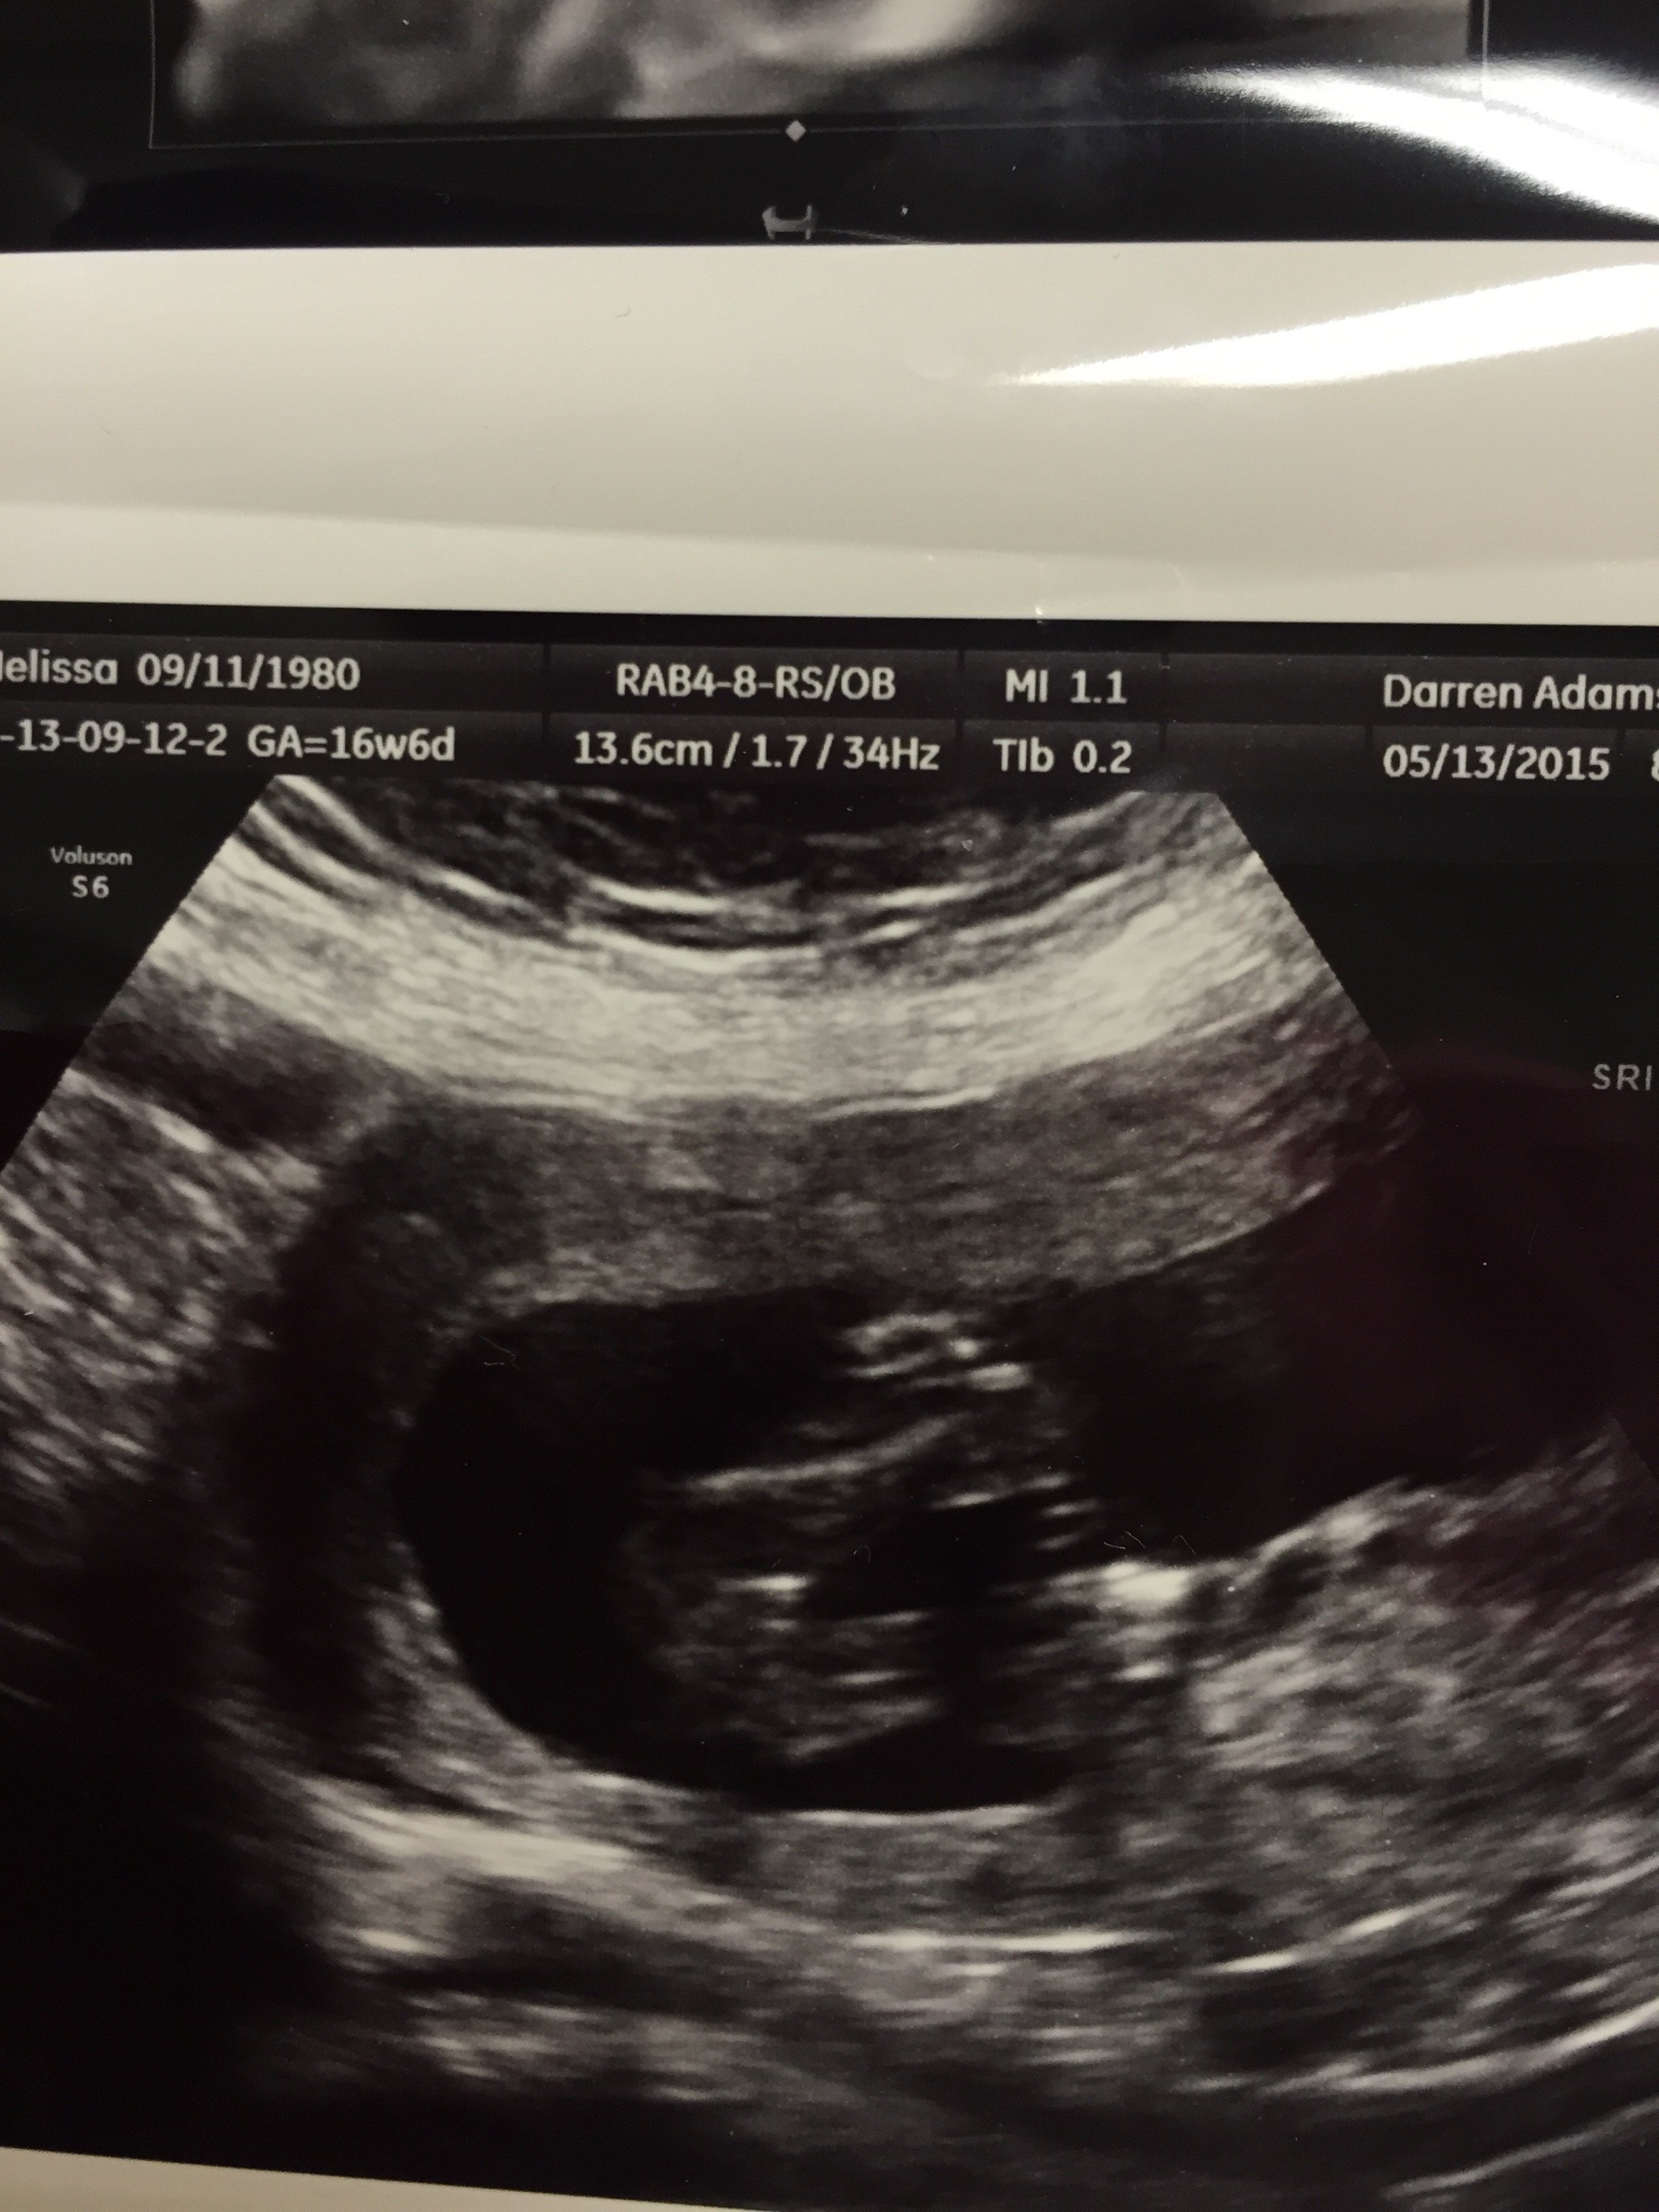

So we had out gender appointment today, and this is the ultrasound. I removed my info, and the words of what they wrote on it because Im very unsure if I believe the tech. (she was an intern and i know that sounds terrible to judge).. but what gender is this to you?

• we were told boy.. and im very annoyed considering I too have heard girl is 3 lines. We have to go back for follow up in 4 weeks because baby was very active, and they didnt get what they needed for other anatomy. it will be interesting but i just wanted to see what others thought and see if i was alone on the girl...

• looks NOTHING like my first son, which is this one.. so i have a hard time believing boy this time

• It was today I am 19w 2days

• My friend owns a 3d ultrasound business and I sent her that pic, she said it was inconclusive you would need more pictures and angles to tell. While 3 lines does mean girl, a boy who is still forming can have the same appearance. I would request another ultrasound!

• It will be a long few weeks! Yes baby was super active, we got this one photo and then one of a hand which was also blurred from movement